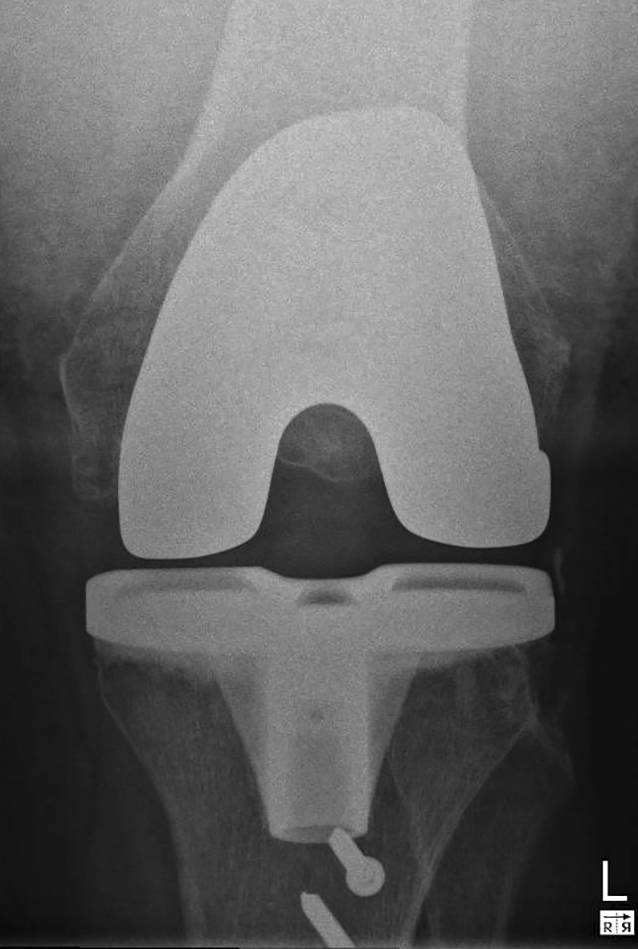

CT-Aufnahmen bieten eine präzisere dreidimensionale Darstellung und liefern genauere Informationen über die Lageverhältnisse der Implantate. Mit einer Spezialsoftware lässt sich die Position der Knieprothesenkomponenten exakt ausmessen (Abb. 4). Dies ist unabdingbar, um eine mechanisch bedingte Ursache der Gelenksteife beurteilen zu können. Auch das Ausmaß und die Größe von Osteolysen und Lockerungssäumen kann man in der CT sensitiver und verlässlicher erkennen als in der Röntgenaufnahme.

Abb. 4

3D-Vermessung einer Knieprothese a koronar (femoral varus-valgus), b koronar (tibial varus-valgus), c seitlich (tibialer Slope), d axial (femorale Rotation)